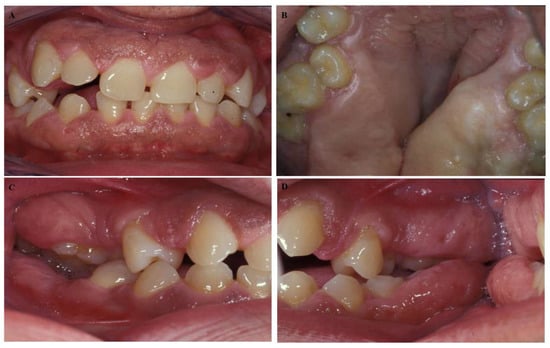

A 50-year-old male presented at the Dental School, University of Seville, with a chief complaint of “gingival swelling all over his mouth”. After the completion of the informed consent, the cases were studied. The swelling caused difficulties in speaking and chewing. No other complaints including pain, bleeding, or halitosis were present. The patient began 4–5 years ago and progressed slowly. His medical history was unremarkable, and he was not taking any medication. His weight and height were within normal limits. An extraoral examination revealed a natural face. The patient could close his lips; however, he was an oral breather. An intraoral examination presented signs of gingival enlargement, a bilateral fullness of the cheeks with painless swelling and palate extension to the midline (Figure 1A–D). We suggested an examination of his family. His wife suffered chronic periodontitis without any gingival enlargement. He had two daughters: one ten years old and the other twelve years old. The younger daughter presented with regular aspects of the gums and the oldest daughter presented with generalized enlargement similar to her father (Figure 2A–D). According to these data, a diagnosis of hereditary gingival fibromatosis was established. The treatment consisted of a rigorous oral hygiene program in addition to professional debridement and gingivectomy at both maxillary quadrants.

Figure 1.

Intraoral images of a 50-year-old male. We observed (A) malocclusion with an anterior open bite, (B) rotation, tooth migration, (C,D) diastemas, malposition and severe gingival enlargement that caused difficulties in speech, mastication, and hygiene.